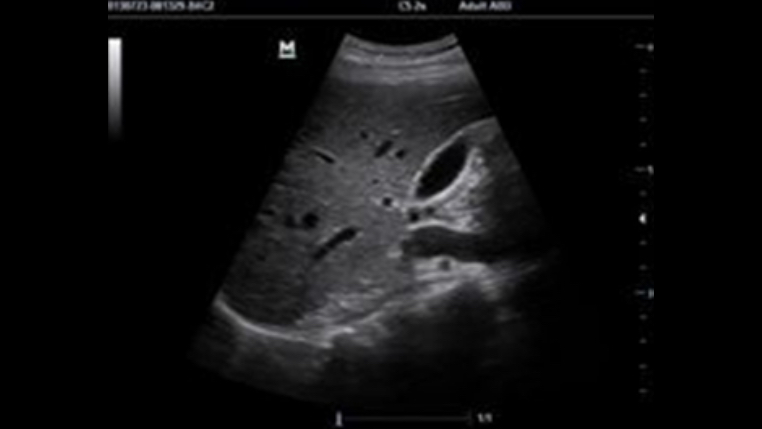

Tissue Doppler Imaging with Quantitative Analysis (TDI and TDI-QA)

Supported by MindrayŌĆÖs unique 3T technology with single crystal, the M7 premium significantly improves the performance of Tissue Doppler Imaging. With the added quantitative analysis package with comprehensive parameter outputs such as velocity, strain and strain rate, the TDI-QA performs with ease at the bedside.